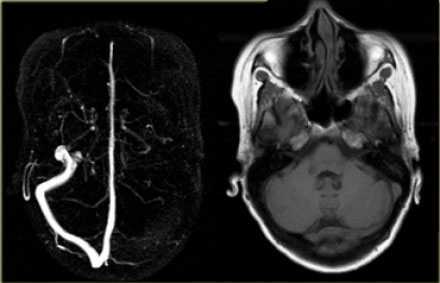

Исключали клинически значимую кардиологическую и лёгочную патологию. Обработку полученных данных проводили при помощи пакета статистических программ SPSS 10 с использованием критериев Стьюдента и Манна - Уитни. Результаты и их обсуждение. Учёт венозной фазы кровотока при МРТ-реконструкции сосудов головного мозга позволил верифицировать варианты развития поперечного и сигмовидного венозных синусов в виде их гипоплазии (рис.1) и полной аплазии (рис. 2).

Рис. 1. МРТ-визуализация сосудов головного мозга с венозной фазой мозгового кровотока. Гипоплазия левого сигмовидного и поперечного венозных синусов головного мозга. Существенное снижение кровотока в левых сигмовидном и поперечном синусах. Асимметрия кровотока в яремных венах - 86 и 14 %

Рис. 2. МРТ-визуализация сосудов головного мозга с венозной фазой мозгового кровотока. Отсутствует кровоток в левых сигмовидном и поперечном синусах. Асимметрия кровотока в яремных венах - 98 и 2 % (аплазия синусов)